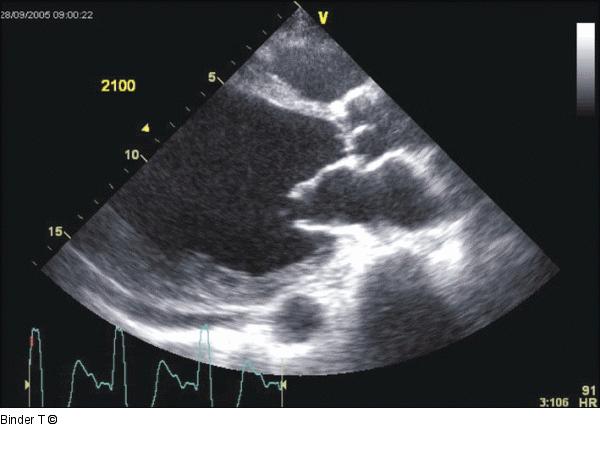

Abbildung 3: Parasternale lange Achse Deutlich dilatierter linker Ventrikel, mit höhergradig reduzierte LVF. Die Wanddicke ist in den einsehbaren Abschnitten erhalten (keine Narbe) Dyssynchronie der Kontraktion ist erkennbar. Myopathisches Bewegungsmuster der Mitralklappe (Folge der reduzierten LVF). Kleiner Perikarderguß. |

Abbildung 3: Parasternale lange Achse

Deutlich dilatierter linker Ventrikel, mit höhergradig reduzierte LVF. Die Wanddicke ist in den einsehbaren Abschnitten erhalten (keine Narbe) Dyssynchronie der Kontraktion ist erkennbar. Myopathisches Bewegungsmuster der Mitralklappe (Folge der reduzierten LVF). Kleiner Perikarderguß. |